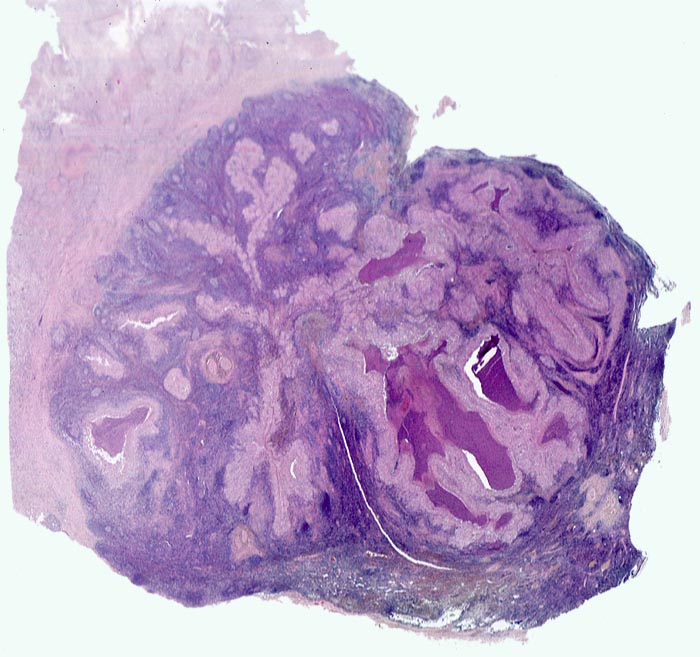

Morphologie:

In der mittleren Dermis bilden sich Nekroseareale, welche von palisadierenden Histiozyten, mehrkernigen Riesenzellen und eosinophilen Granulozyten demarkiert werden. Die regionären Lymphknoten zeigen ebenfalls eine retikulozytär abszedierende Entzündung. Diese ist jedoch nicht spezifisch. Sie kommt auch vor bei Yersiniose, atypischer Mykobakteriose, Sporotrichose, Tularämie, Tumoren, Lymphogranuloma venereum und Coccidiomykose.